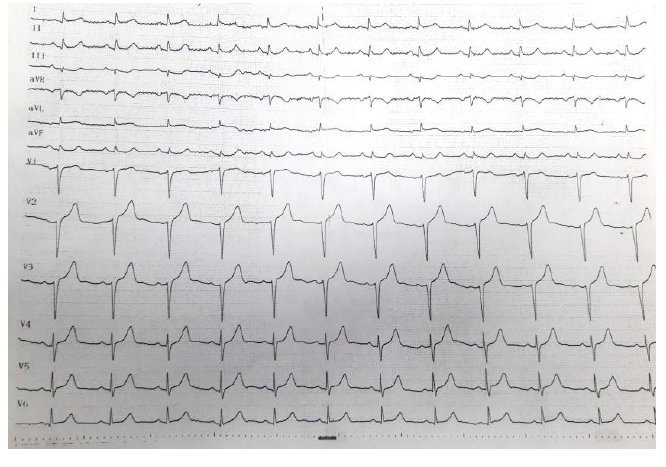

A 65-year-old female admitted to the Central Military Hospital (HMC) for a 24-hour period of progression consisting of slow onset thoracic pain with maximum intensity at the hour after emotional, oppressive, retrosternal, intense, irradiated stress upper limb and neck, associated with dyspnoea and dysautonomic symptoms. Consultation at a health center where studies are carried out with non-diagnostic electrocardiogram (Figure 1), report of a cardiac biomarker that is positively elevated, 5 times the cut-off point and echocardiogram with segmental disorders of contractility. Treatment is started for Acute Coronary Syndrome without Elevation of the ST Segment and refer to our institution.

Figure 1 Initial electrocardiogram

With the findings of the echocardiogram, the patient is taken to a coronary arteriography where no significant lesions are documented and in the ventriculogram an apical abalonamiento with significant involvement of the ejection fraction is observed. Takotsubo syndrome was considered compatible, so the pharmacological management of the patient was adjusted and a new assessment was scheduled with electrocardiogram (Figure 3) and transthoracic echocardiogram at the month of the event.

Figure 3 Control electrocardiogram at the month of the event.